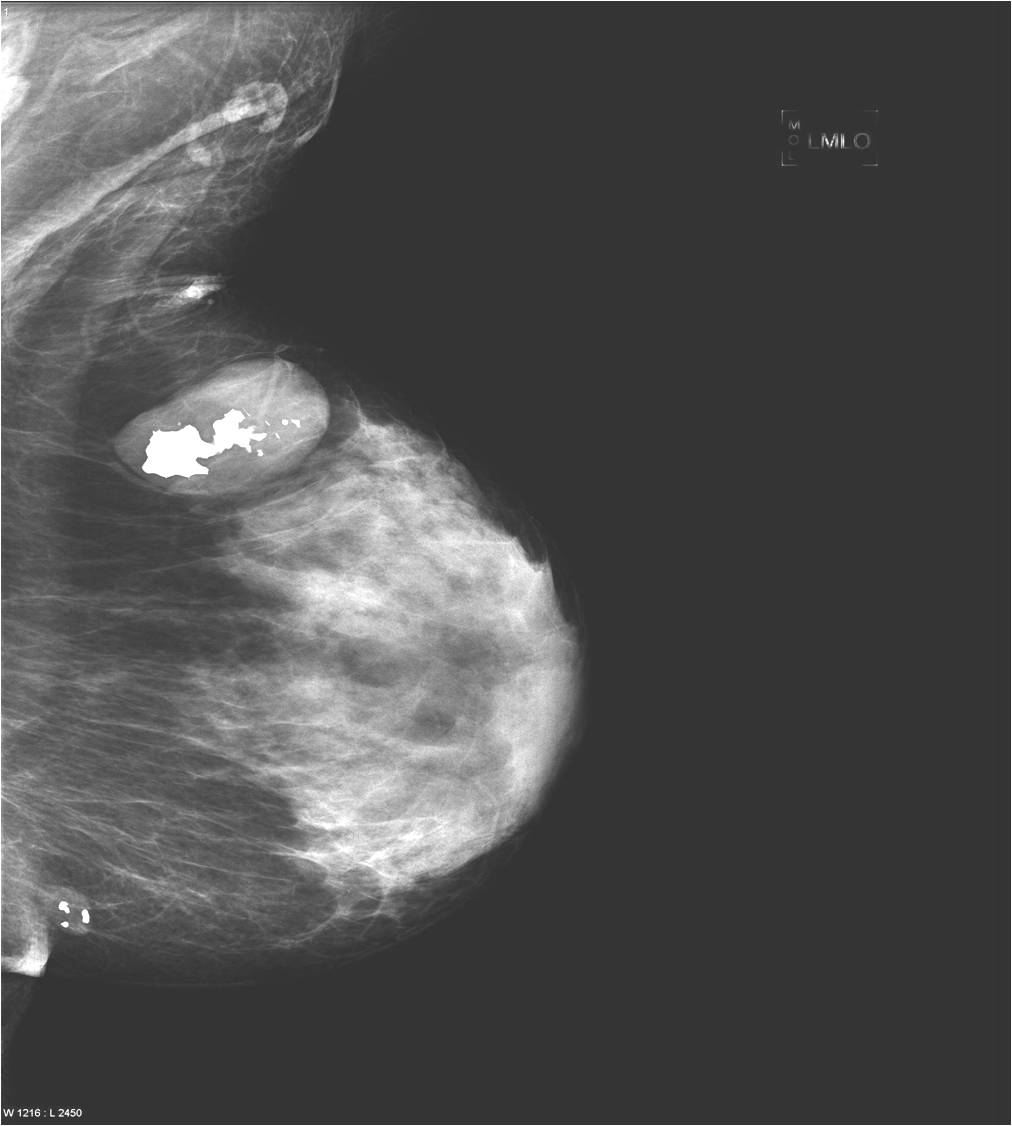

2. Digital mammography has displaced the analogue technic for today almost everywhere: (pictures 1,2,3) phosphorous plate or direct digital methods. For breast imaging the latter is the method of choice. Phases of image production separate. The image is produced on the detectors, but appears on the high resolution monitor and can be stored as a digital data set at various storage mediums (e.g.: CD, hard disk drives).

Image

Picture 1.